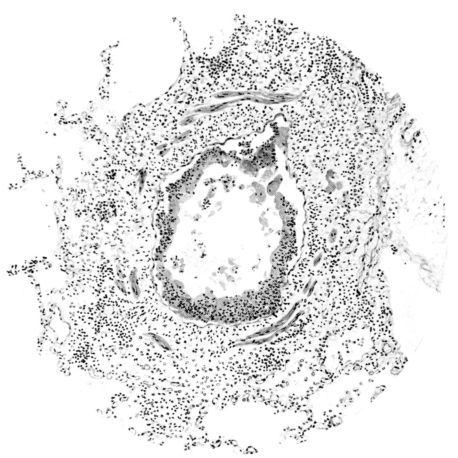

FIG. IV. AUTOPSY NO. 205. CONGESTION AND EDEMA OF THE SUBMUCOSA AND REGENERATION OF THE TRACHEAL EPITHELIUM.

The changes are less marked, perhaps, in the trachea than in its finer ramifications. The mucosa is constantly more or less destroyed and large areas, usually focal, are entirely devoid of their epithelial covering. This is replaced by a sparse exudate, composed largely of red blood cells, mucus, a small amount of fibrin, and nuclear fragments (Fig. II). It may dip into the submucosa for a short distance, but usually these indentures are associated with the ducts of the mucous glands into which the inflammatory reaction extends. A more striking feature than the exudate, however, is the edema and the congestion of the submucosa. The loose areolar tissue of the submucosa is spread widely apart, and throughout it distended blood vessels are very conspicuous. Occasionally such a vessel is broken and actual hemorrhage appears in the submucosa. Occasionally, too, the inflammation extends down the duct to the mucous gland itself, and here, also, aplastic inflammatory reaction is evident, inasmuch as the acini now stain intensely red with the cells undifferentiated from each other and specked here and there by broken remains of the dead nuclei (Fig. III). After the disease has continued for a short period, even at the end of five or six days, some regeneration of the epithelial lining may be seen (3) (Fig. IV). But despite this, the acute picture persists, and there goes on, side by side, an attempted repair characterized by epithelial regeneration and the same evidence of acute change. Since the lesion is essentially a superficial one, scars or contractures of any extent are not encountered in the trachea, even in examples of the disease that have ended fatally only after many weeks.[4]